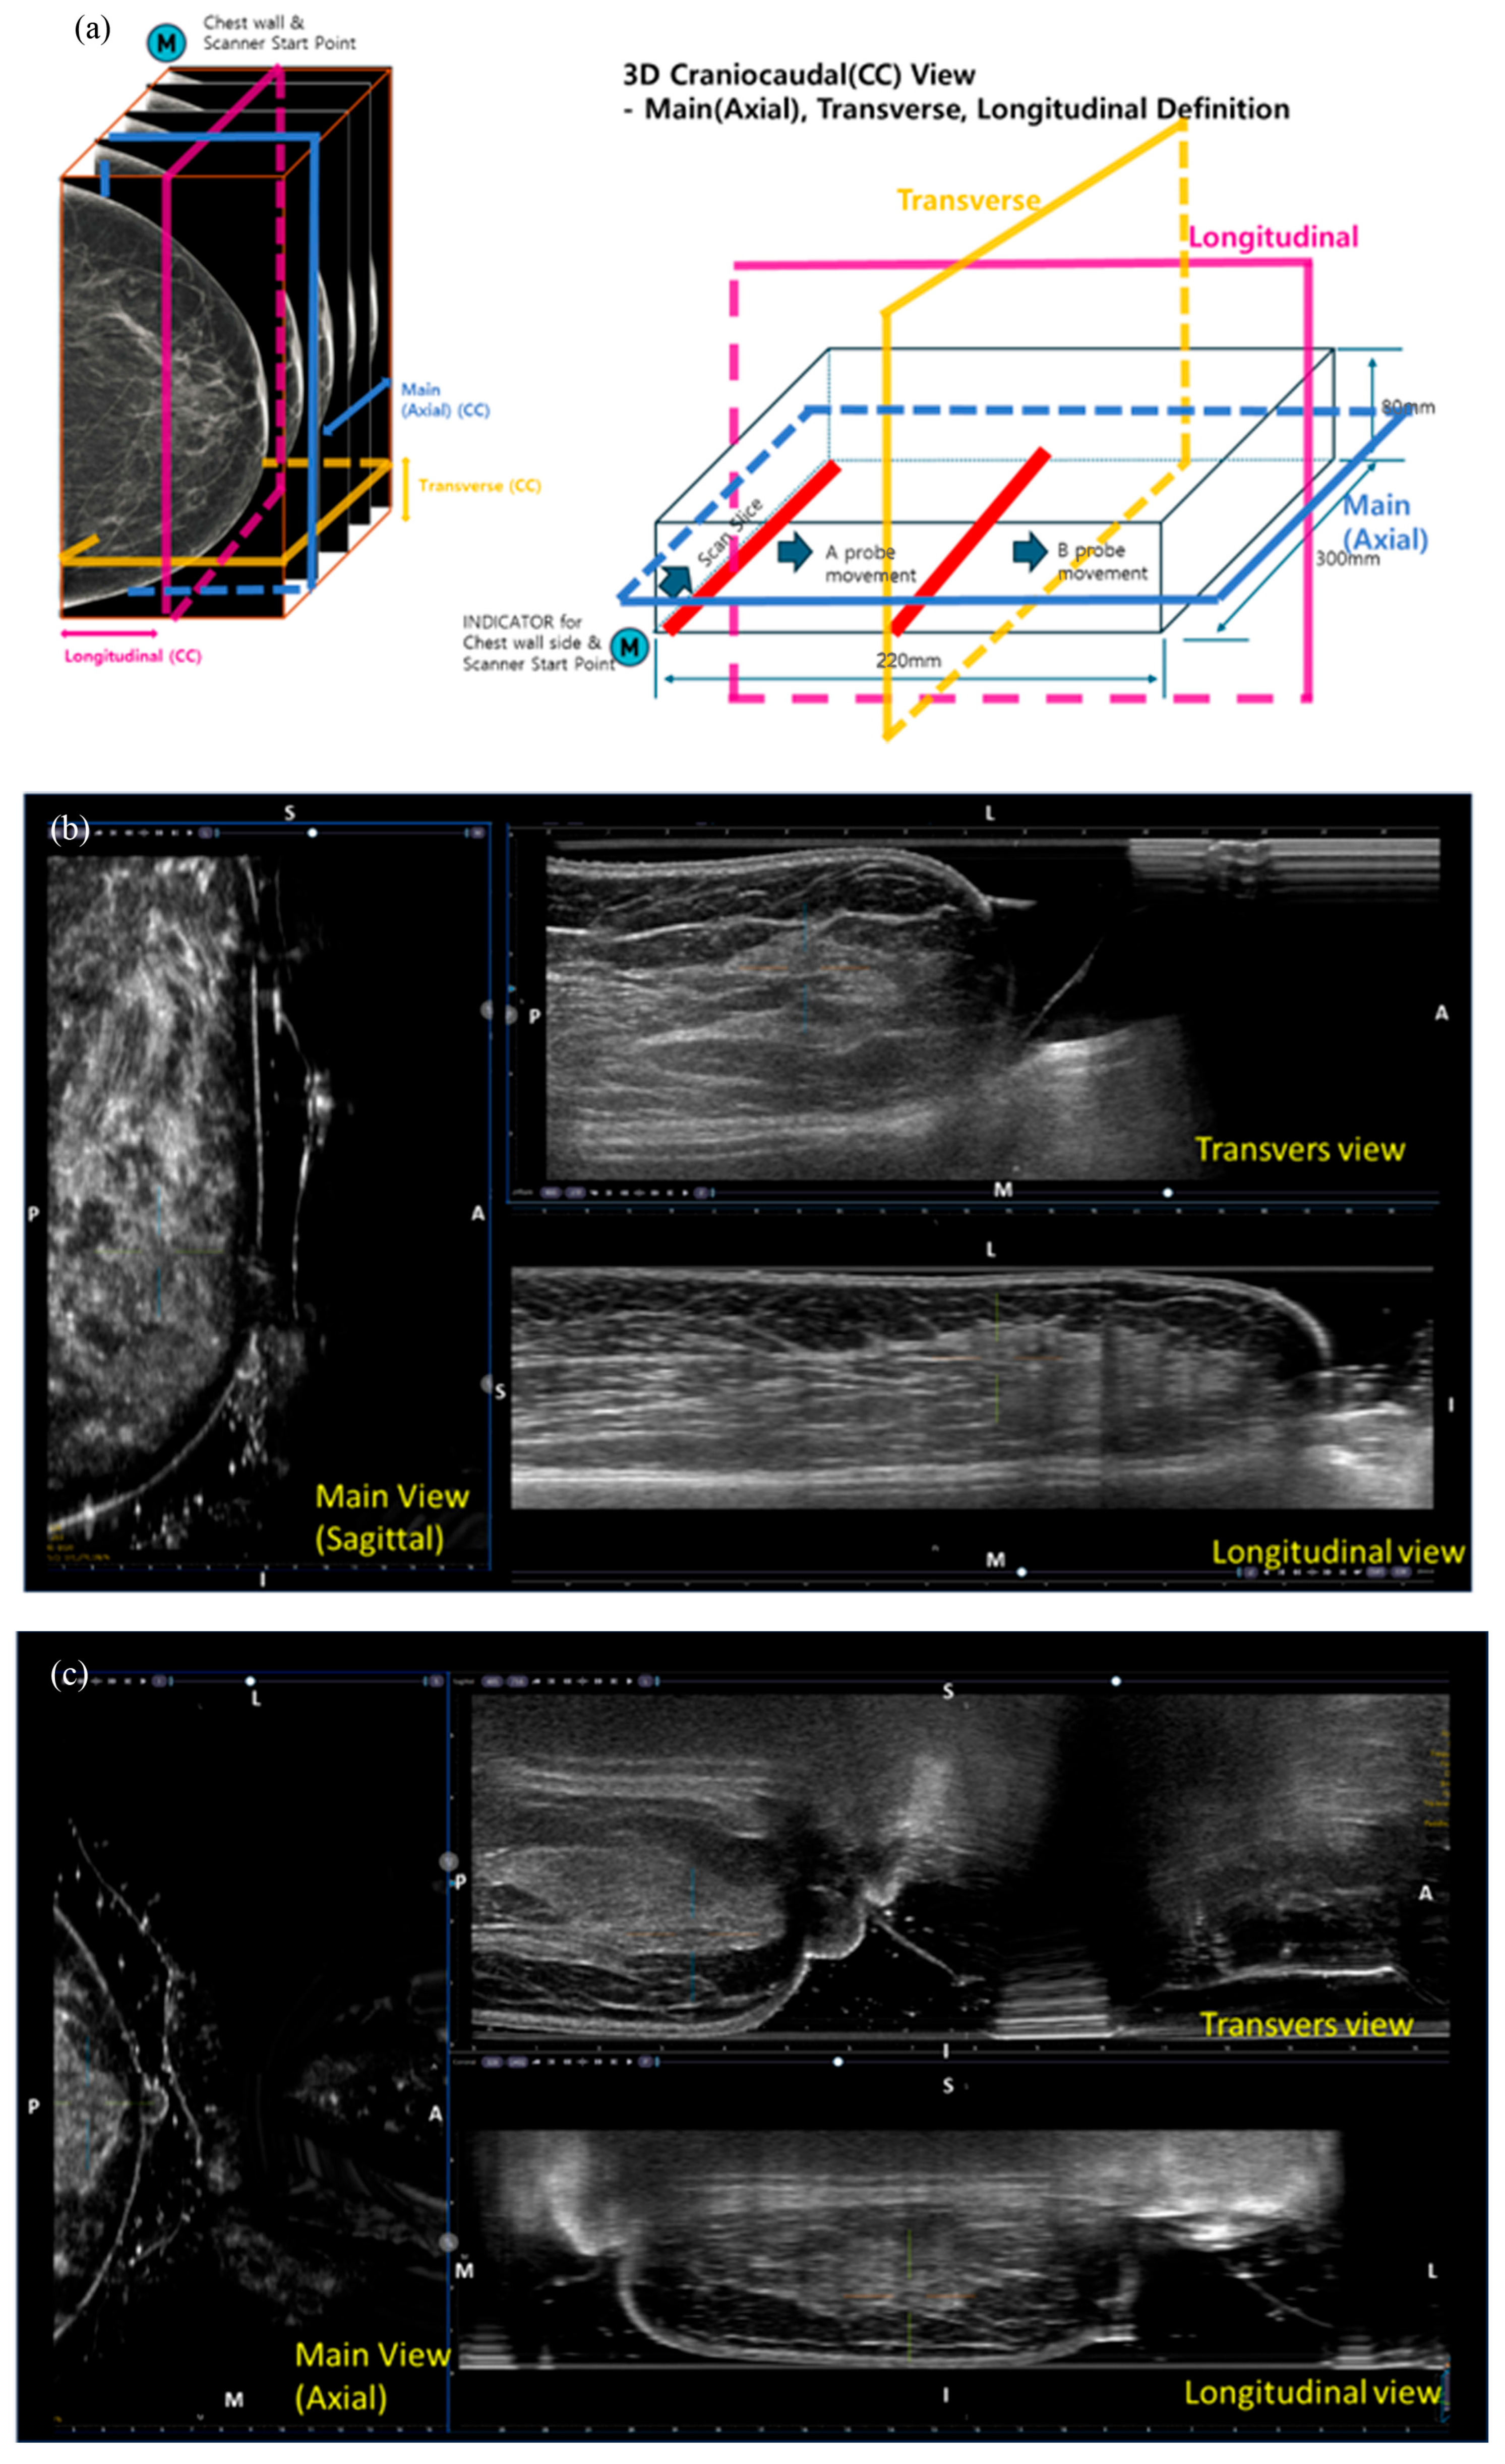

2.4. MammouS-N

All MammouS-N assessments were performed by one of three radiology technologists, each extensively trained in both ABUS and mammography, using the MammouS-N system (Medicalpark, Yongin, Republic of Korea). The MammouS-N scan was fully automated and continuous, utilizing a 5–12 MHz wide-aperture linear probe to cover an area of up to 30 × 22 cm, with a maximum penetration depth of 8 cm (Figure 1 and Figure 2). Each scan generated approximately 800 slices per volume at an 8 cm depth and 1280 slices at a 2 cm depth.

MammouS-N images were acquired with the patient in a standing position using two projections analogous to the CC and MLO mammography views. For the CC view, the ultrasound probe was positioned inferiorly with breast compression, whereas for the MLO view, it was positioned laterally (Figure 3). In the posteroanterior view (Figure 3), the patient faced the probe with a tightly compressed breast. Ultrasound gel was applied to ensure smooth contact between the probe and the breast.

Volume images were automatically transferred to a dedicated workstation. Volumetric data were acquired in the transverse plane, with slice thicknesses of 0.25–0.4 mm. The pixel spacing was 0.04 mm at the 2 cm depth and 0.06 mm at the 8 cm depth. The main viewing plane (axial) was automatically reconstructed with a uniform pixel size of 0.1 mm across all depths.

Figure 3. Images of the MammouS-N system: (a) Multiplanar views (axial, transverse, and longitudinal) corresponding to mediolateral, craniocaudal, and posteroanterior volumes. (b) Mediolateral oblique view: The left image shows the sagittal view corresponding to a mammographic mediolateral oblique projection. The upper-right and lower-right images represent transverse and longitudinal views, respectively. (c) Craniocaudal view: The left image shows an axial view corresponding to the mammographic craniocaudal projection. The upper-right and lower-right images show transverse and longitudinal views, respectively. (d) Posteroanterior view: The upper right image corresponds to the transverse ultrasound view, the lower right to the longitudinal view, and the left to the coronal view. Orientation markers are shown consistently across images: A = anterior, P = posterior, M = medial, L = lateral, S = superior, and I = inferior.